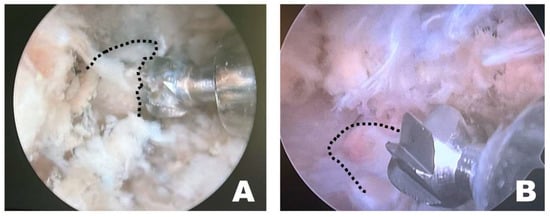

Instrument handling during osteotomy differed depending on the surgical approach (Figure 7). When the procedure was performed on the left side of the dog, the osteotomy was initiated by anchoring the burr to the wider caudal portion of the accessory process, which allowed stable initial anchorage during progressive bone removal. In contrast, when the procedure was performed from the right side, the initial anchorage was less stable, and osteotomy was more frequently initiated from a more central portion of the accessory process. All procedures were performed with the dogs maintained in the dorsoventral position by a right-handed surgeon.

Figure 7.

Endoscopic observation, depending on the side of the surgical intervention site. (A) On the patient’s left side, the osteotomy was initiated by anchoring at the wider caudal portion of the accessory process. (B) On the patient’s right side, the osteotomy was initiated from the middle of the accessory process without secure anchoring. The dashed line indicates the accessory process.

The triangular portal arrangement influenced working space formation and endoscopic visualization (Figure 8). When an appropriate triangular configuration was achieved, a working space was created at the target point, and the tip of the instrument remained consistently visible. In this configuration, instrument manipulation and visualization could be maintained simultaneously within the endoscopic field. In the open triangular configuration, a working space was not formed, and the instruments were not visible. This configuration was associated with failure to establish a functional working corridor at the target point. Although the working space was formed in a closed triangular configuration, it was located away from the target point, and only the shaft of the instrument, rather than the tip, was observed. As a result, precise manipulation at the accessory process was limited despite the presence of a working space.

Figure 8.

Observations of the triangular formation of the endoscope and working instrument from the dorsoventral view of the fluoroscopy. (A) In an open triangle formation, a working space was not created, and the instruments were not visible. (B) In a perfect triangle formation, the working space was appropriately created at the target point, and the visualization of the instrument’s tip was accurate. (C) In a close triangle formation, while a working space was formed, it was not at the target point, and the shaft of the instrument, rather than its tip, was observed. The dashed lines indicate the tips of the endoscope and the working instrument.